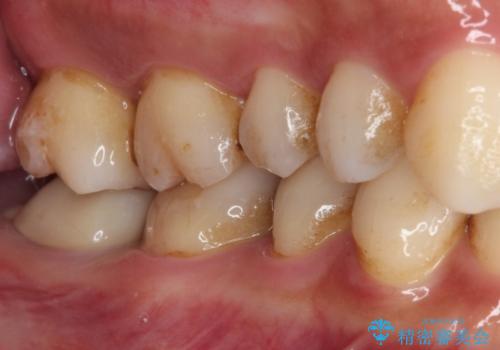

- かかりつけ医にて、歯の高さが不足しているためセラミッククラウンの装着はできないと言われたとのことで来院された患者様です。

診察したところ、確かに歯の高さは不足していましたが、土台の立て直しや歯の削り方を調整することでオールセラミッククラウンでも補綴可能と思われました。

ただし、クラウンの厚みは極力薄くした方が維持力が増すため、高強度のフルジルコニアクラウンにて補綴治療することとしました。

仮歯が途中外れることもなく、無事に補綴治療を行うことができました。

歯石や磨き残しなどが多いため、今後クリーニングを行っていきます。